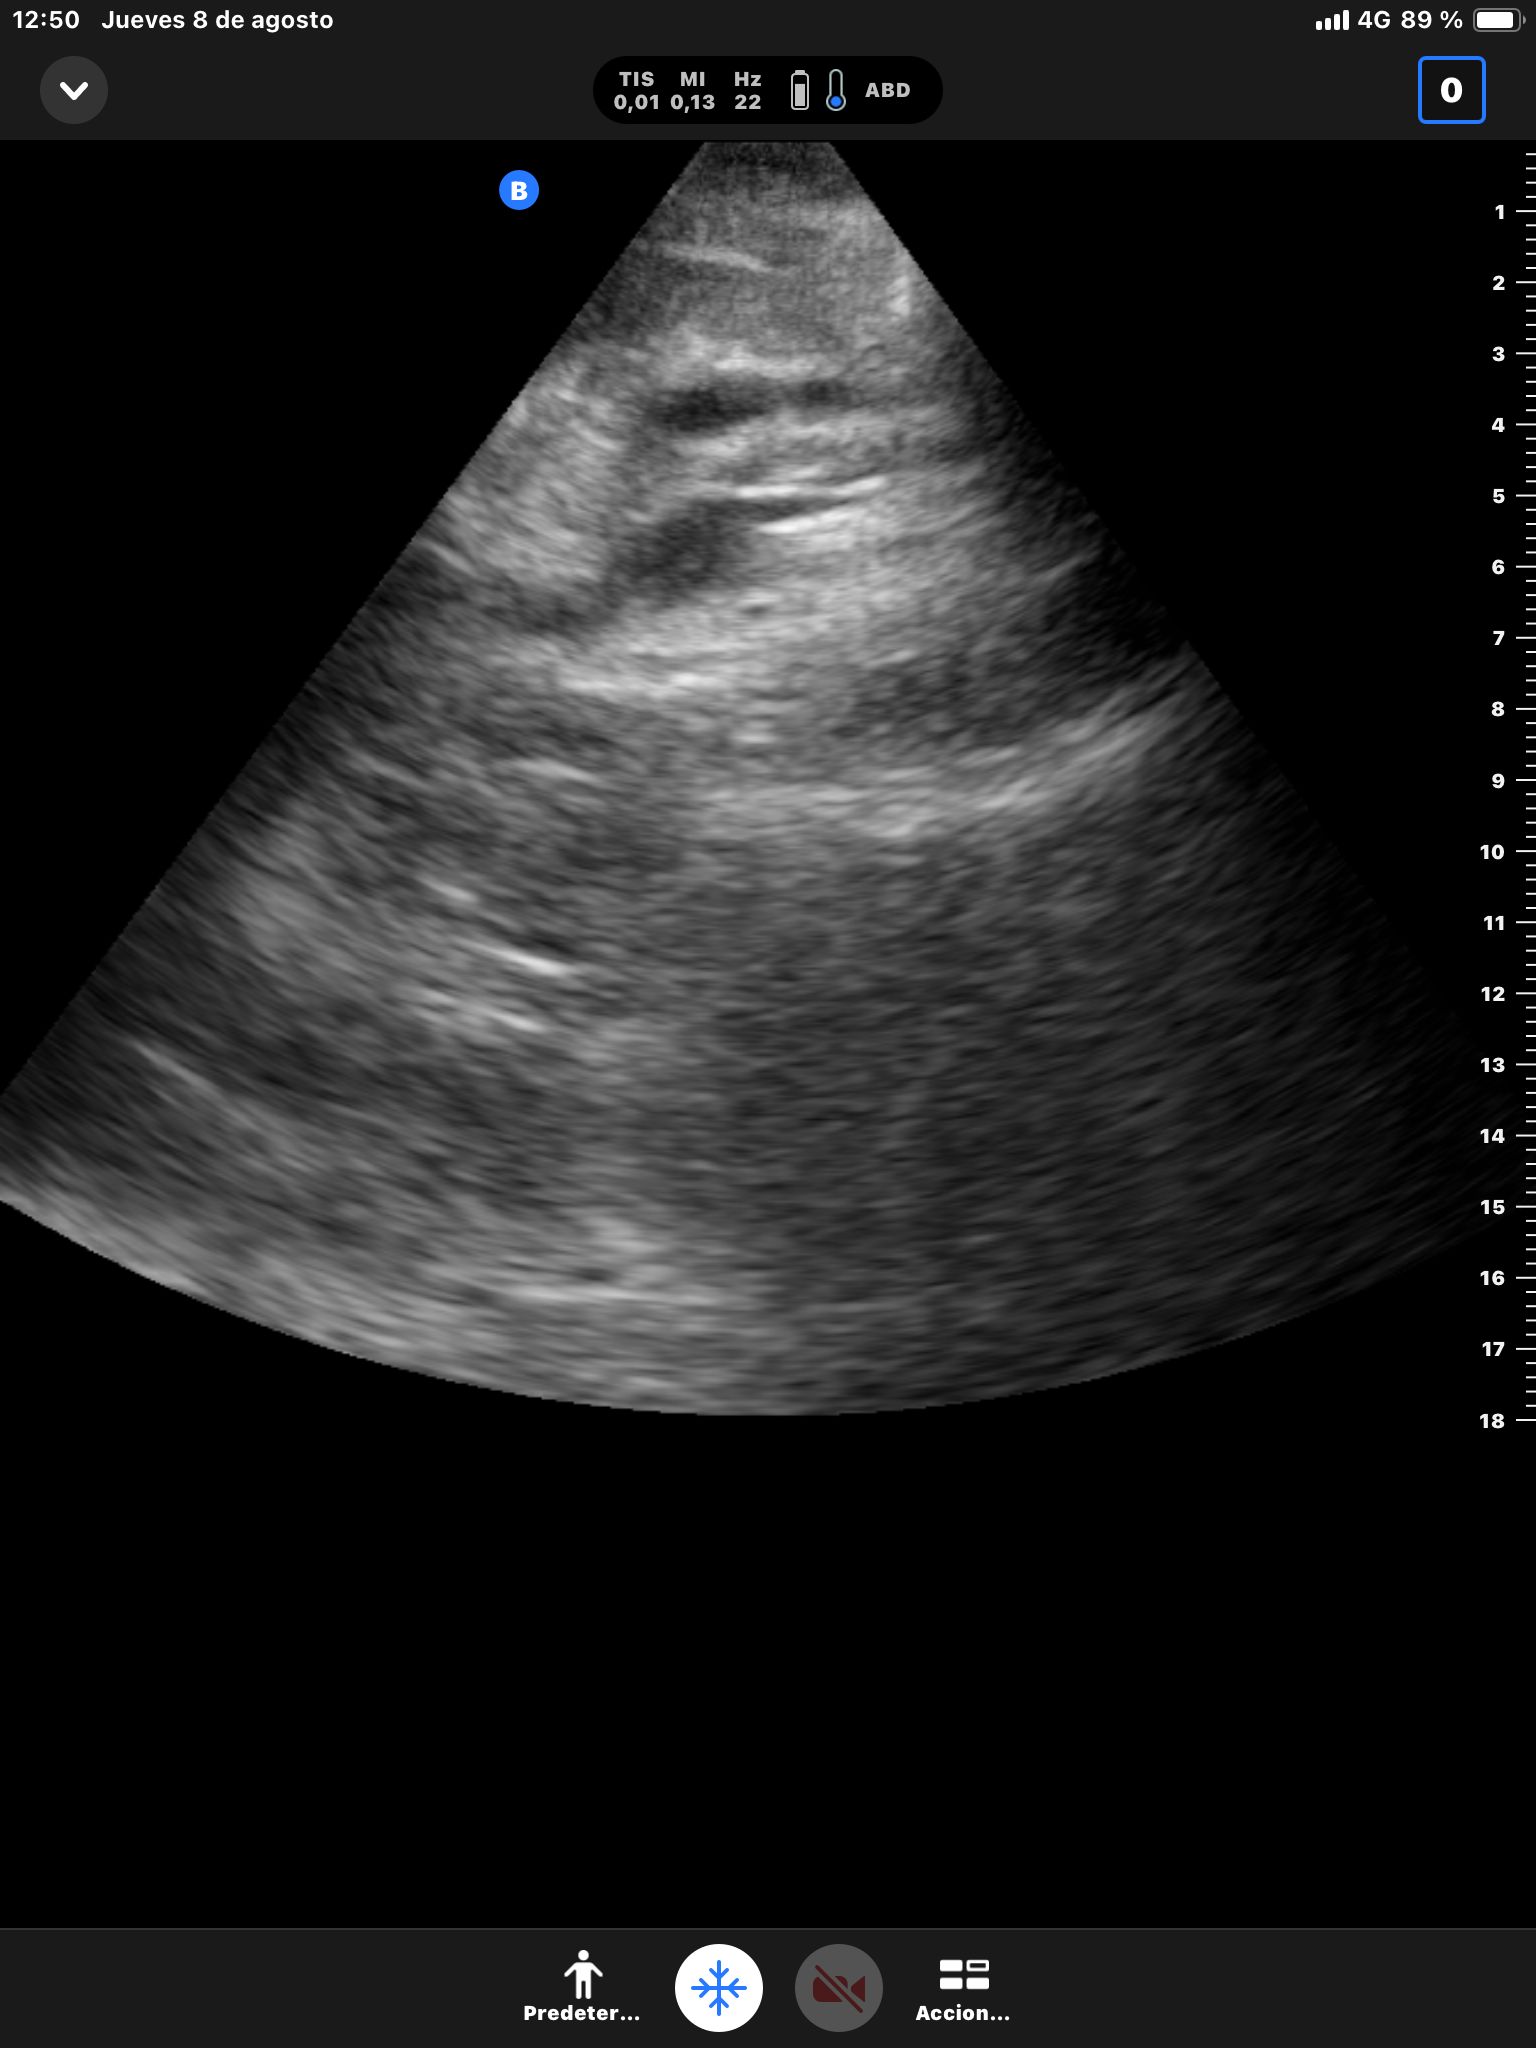

Hígado sin LOEs. Vesícula biliar con hidrops (58 mm), dilatación del colédoco (10 mm). Páncreas hiperecogénico, atrófico, Wirsung de 76 mm.

Dilatación de la vía biliar intrahepática con colédoco dilatado y atrapado por un área hipocaptante sobre la cabeza del páncreas. Atrofia del páncreas con dilatación del conducto de Wirsung que presenta calibres de hasta 8 mm con afilamiento o en el área de la cabeza pancreática.